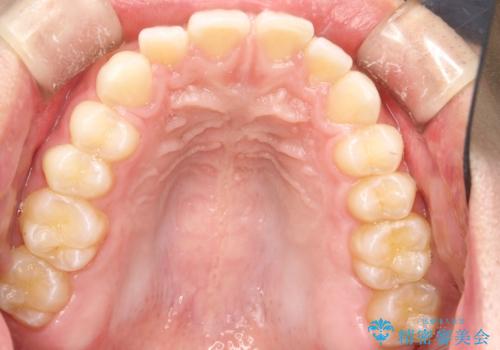

前歯の隙間がきになる インビザラインですきっ歯の治療

- 上の前歯の隙間を主訴に来院されました。

正中に隙間があり、かみ合わせが深い過蓋咬合という状態でした。

インビザラインにて矯正治療を行いました。

しっかり使っていただけたので、スムーズに治療を終了することができました。